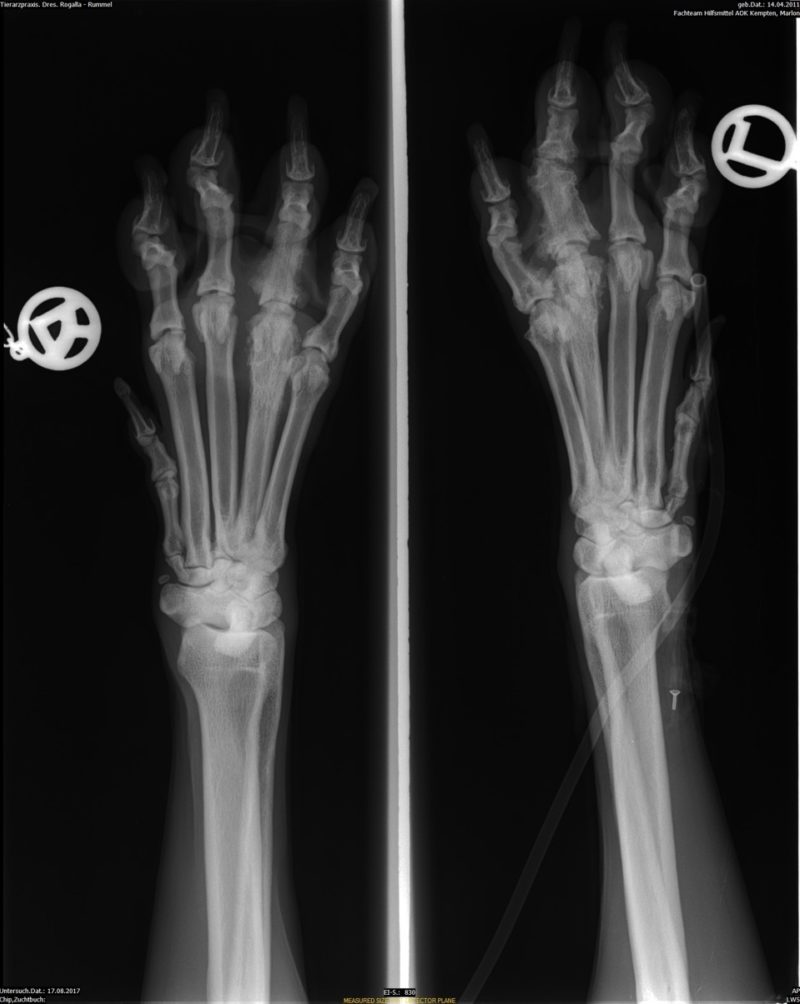

In Narkose wurden Ellbogen, Schulter und Pfoten beidseitig geröntgt. Wie schon vermutet, lag das Problem nicht am Ellbogen, vielmehr waren die Zehengelenke der linken Pfote arthrotisch verändert (Polyarthrose). Ich wählte für Marlon jetzt ganz besondere Akupunkturpunkte aus, um seine Schmerzen zu nehmen. Mit einem kleinen Trokar wurden die Goldbits in diese Punkte implantiert, (funktioniert ähnlich wie das Setzen eines Mikrochips) - die kleinen Einstichstellen verheilten schnell.